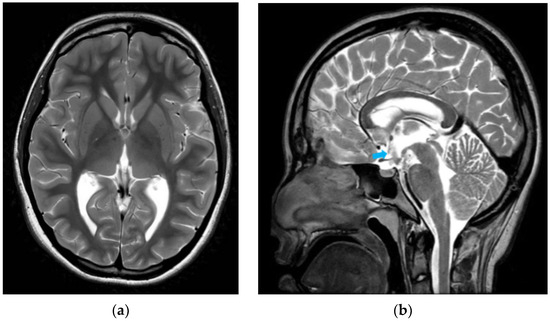

Hyponatremia Following Endoscopic Third Ventriculostomy in an Adolescent with an Aqueductal Web: A Case Report

by Tingting Feng, Lee Ping Ng, Wan Tew Seow and Sharon Y. Y. Low

Reports 2026, 9(2), 122; https://doi.org/10.3390/reports9020122 - 17 Apr 2026

Background and Clinical Significance: Endoscopic third ventriculostomy (ETV) is a well-established cerebrospinal fluid (CSF) diversion technique for treating obstructive hydrocephalus. Here, the complication of post-ETV hyponatremia is rare. Separately, aqueductal web as a cause of obstructive hydrocephalus is also an uncommon occurrence. We [...] Read more.

Background and Clinical Significance: Endoscopic third ventriculostomy (ETV) is a well-established cerebrospinal fluid (CSF) diversion technique for treating obstructive hydrocephalus. Here, the complication of post-ETV hyponatremia is rare. Separately, aqueductal web as a cause of obstructive hydrocephalus is also an uncommon occurrence. We present an unusual case of an adolescent who presented with late symptoms of obstructive hydrocephalus secondary to an aqueductal web and developed a delayed onset of post-operative hyponatremia after a successful ETV procedure. Pertinent aspects of the case are discussed in corroboration with the recent literature. Case Presentation: A previously well 14 year old presented with symptoms of raised intracranial pressure. Neuroimaging demonstrated progressively enlarging ventricles associated with an aqueductal web. She underwent an uneventful ETV and was discharged home. However, she was readmitted for symptomatic hyponatremia that was investigated and most likely attributed to Syndrome of Inappropriate Antidiuretic Hormone Secretion (SIADH). She was managed with fluid restriction with good clinical improvement. Conclusions: We herein report a case of delayed onset of obstructive hydrocephalus secondary to an aqueductal web, treatment challenges faced and the patient’s unexpected occurrence of hyponatremia after a technically successful ETV. This emphasizes that clinicians need to be mindful of this potential post-operative complication and the ability to discern subtle symptoms in a patient whose clinical signs may not be straightforward. Full article